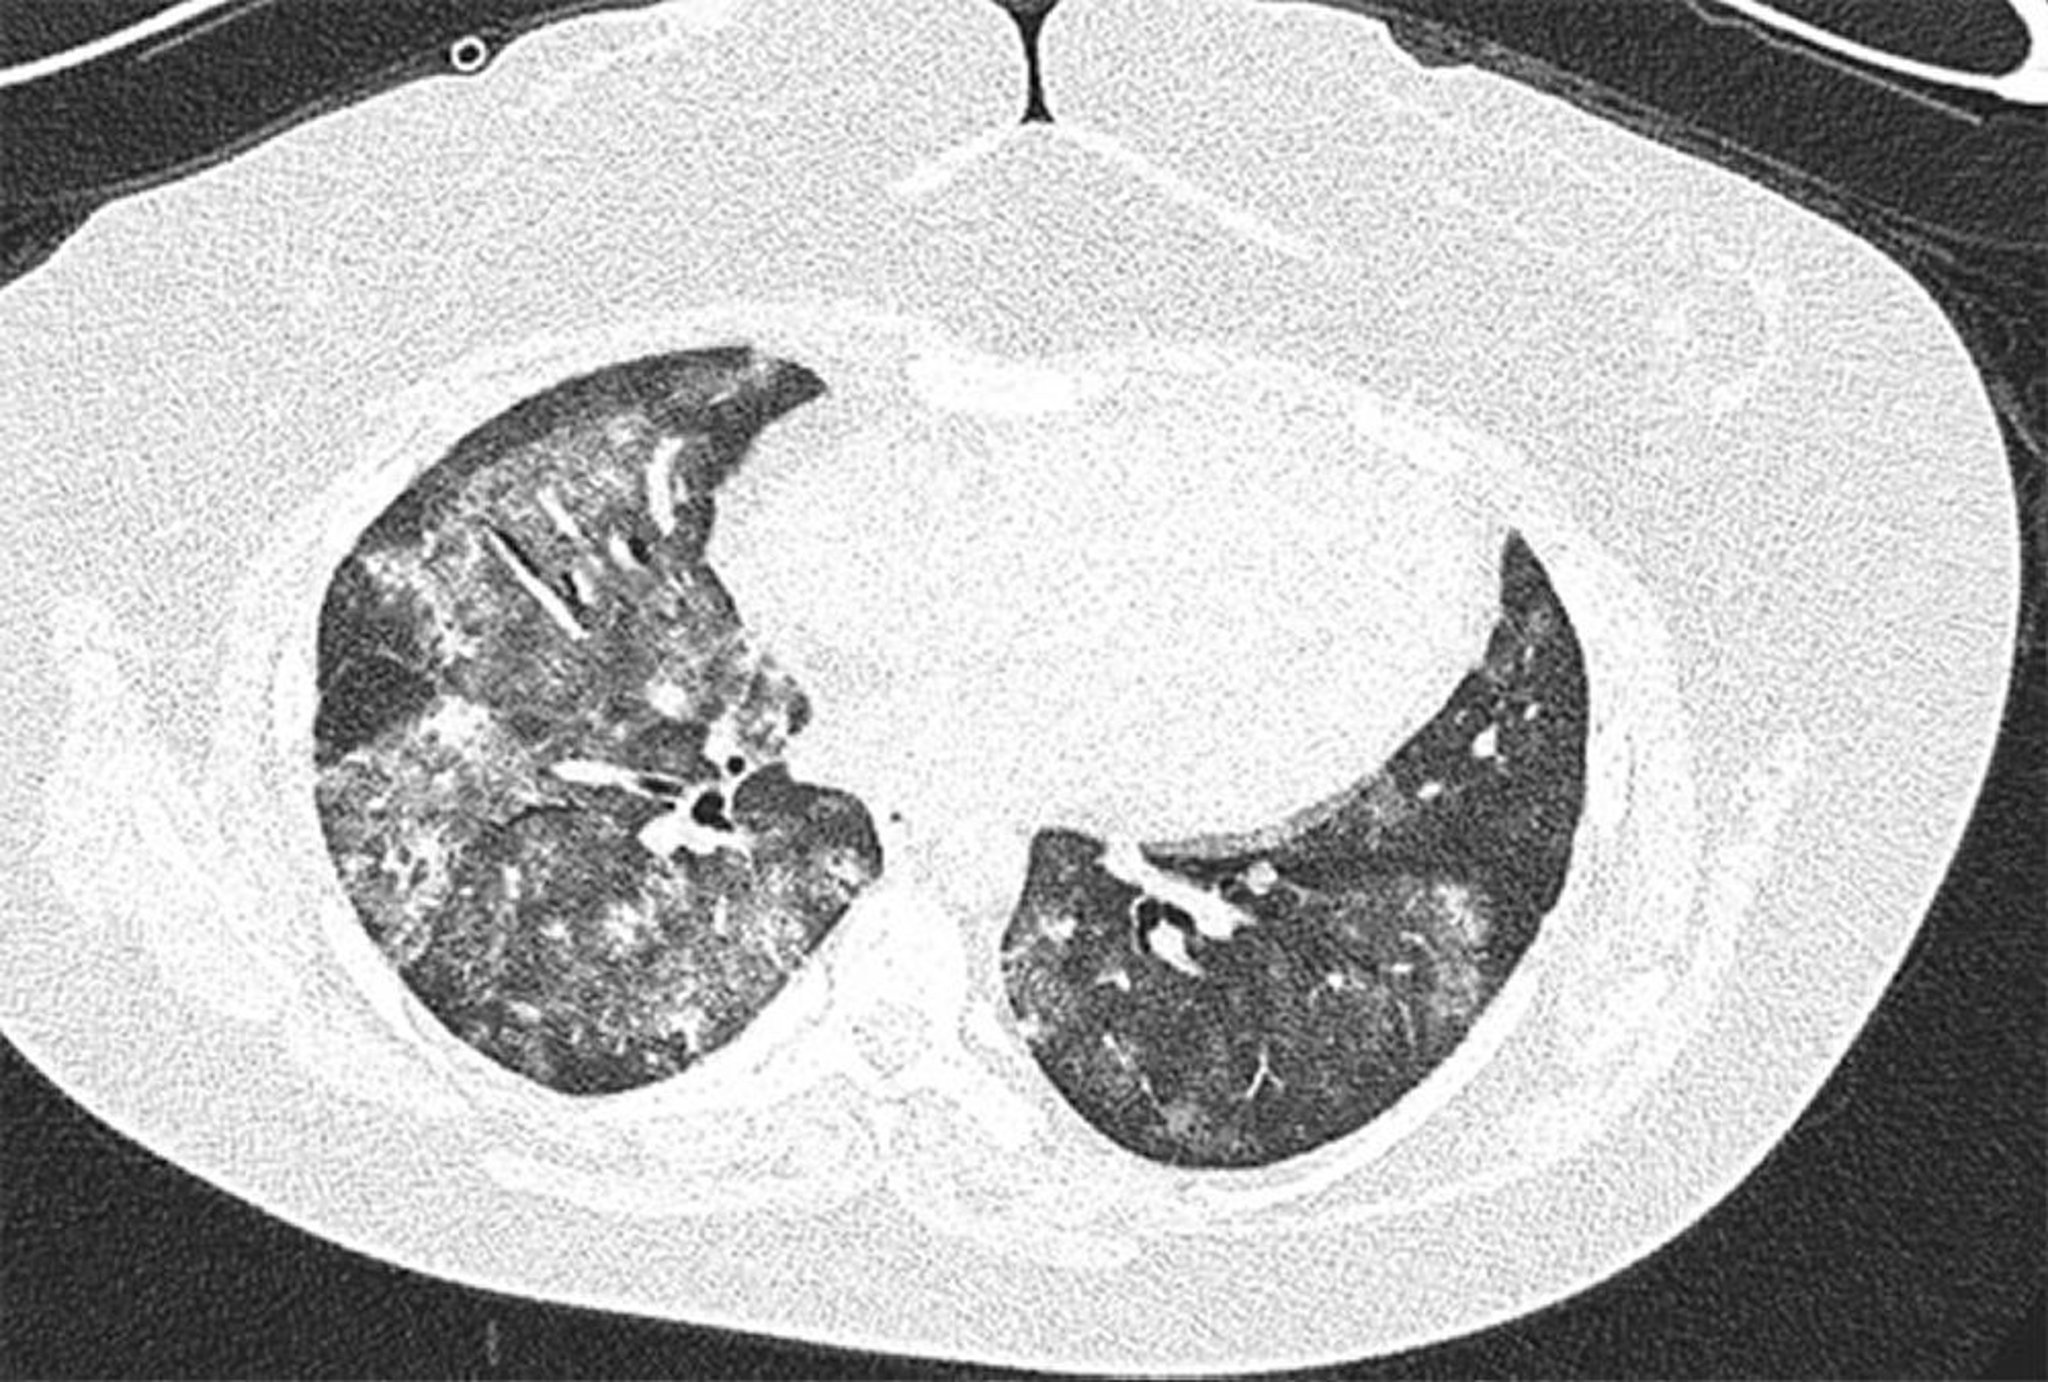

Diffuse alveoläre Hämorrhagie

Hochauflösendes CT-Bild einer 28-jährigen Frau mit Antiphospholipid-Syndrom und rezidivierender diffuser Alveolarblutung. Das Bild zeigt beidseitige und fleckige alveoläre Grundglastrübungen mit subpleuraler Verschonung. Bronchoalveoläre Lavage bestätigte alveoläre Blutung.

Image courtesy of Joyce Lee, MD.